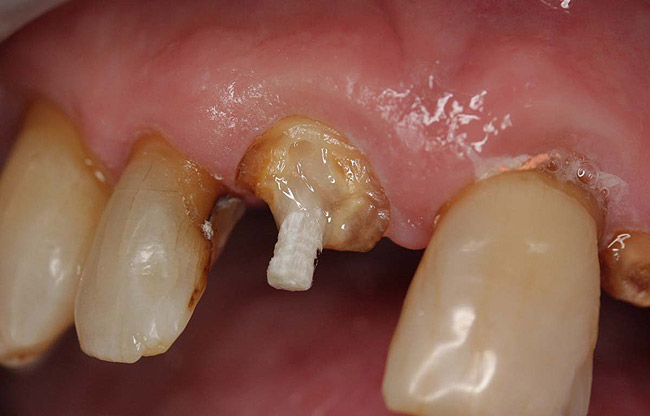

A Class IN maxillary bicuspid was previously restored with a fiber post and an all-porcelain crown (Figure 1). The forces of the oral environment resulted in fracture of the fiber post and crown failure. The remaining fiber post in the root was removed, and anti-rotational areas were prepared for a cast post (Figure 2). A gold cast post was constructed at a dental laboratory, using an indirect technique (Figure 3). A porcelain-fused-to-metal (PFM) crown was constructed with a bevel finish to provide a ferrule and reduce forces on the post (Figure 4 and Figure 5).

Figure 2  Same second bicuspid as Figure 1 after removal of the fractured fiber post.

Figure 2

Figure 3  Cast post to restore the second bicuspid.

Figure 3